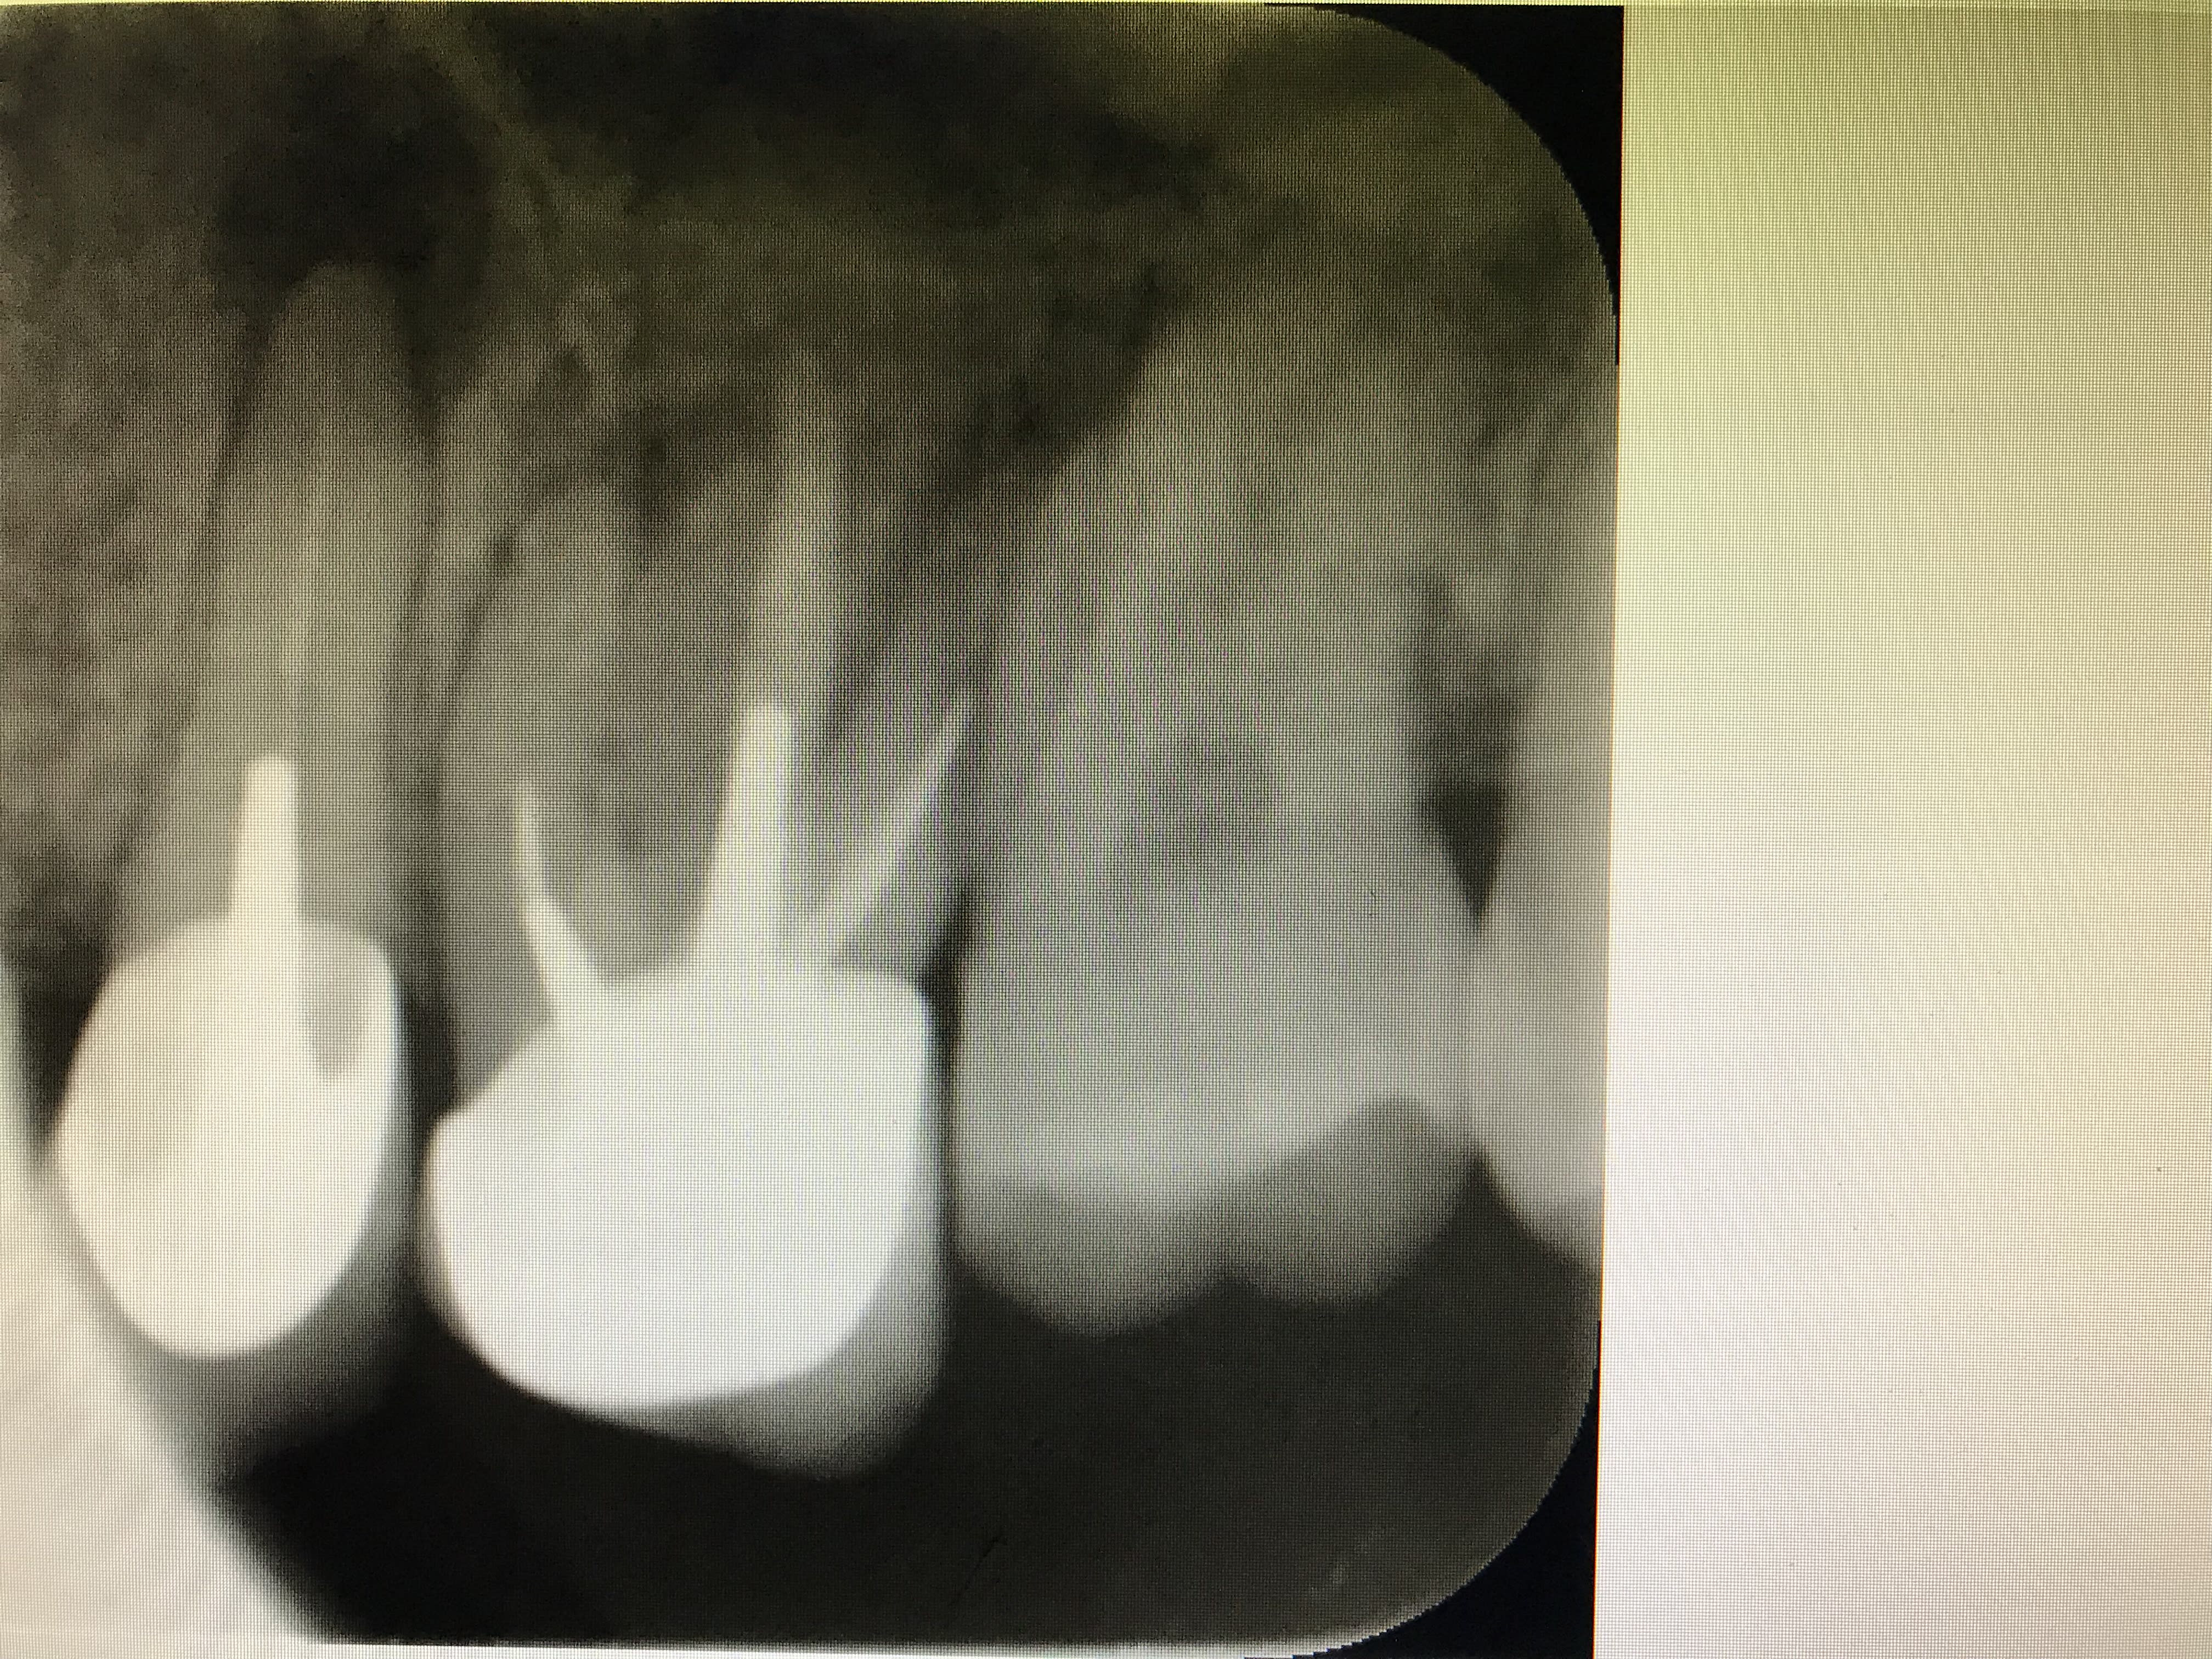

27/02/2018 à 16h56

allez ne soyons pas sectaire que j'me dis. Si Enlaye le fait avec les dents, pourquoi pas avec un implant.

patient que je reçois en mai dernier , 93 ans, aucune hygiène, et beaucoup de soins dentaires. il vient pour autre chose, mais me parle aussi de son bridge mandibulaire droit qui bouge. je touche à peine et je me retrouve avec le bridge dans la main. le pilier distale est descellé, mais en mesiale j'ai l'implant qui vient avec le bridge. un coup de rincette avec la seringue du fauteuil, un peu de ciment en distal et je repose le tout dans l’alvéole. je revois le patient plus tard pour faire l'endo sur la 43..

la première radio date de mai, la deuxième a été faite cette semaine .

maintenant, l'augmentation de la densité osseuse est peut être une illusion du à la radio..

même pas, j'ai juste reposé dans l'alvéole après avoir rincé pour enlever la salive sur l'implant..